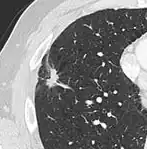

• Pleural retraction is far more common in cancers.[9] It is the pulling of visceral pleura towards the nodule.[9]